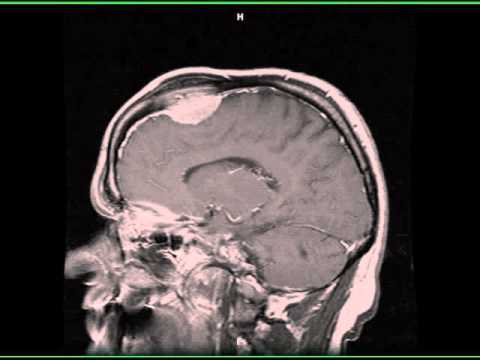

Hellow guys, Welcome to my website, and you are watching Giant meningioma of left cerebellopontine angle. and this vIdeo is uploaded by Neurosurgery TV at 2016-04-11T11:17:22-07:00. We are pramote this video only for entertainment and educational perpose only. So, I hop you like our website.